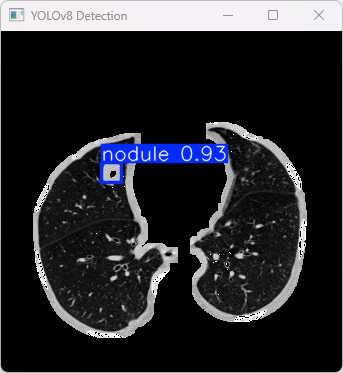

4.检测结果识别

模型训练完成之后, 我们将能够生成一份最优的训练成果报告, 其中包含了编号为best.pt的模型文件, 该文件夹位于runs/train/weights这一特定路径中. 在完成上述操作后, 我们还可以依此文件为基础开展后续步骤中的推理分析工作

此代码的作用是导入预训练好的YOLOv8模型架构,并针对指定输入图像执行目标识别操作后输出相应的检测结果

执行imgTest.py代码后,会将执行的结果直接标注在图片上,结果如下:

此段输出基于YOLOv8模型针对图片' image.jpg '进行了检测结果展示如下

图像信息:

(1)涉及的图像路径是:E:\PulmonaryNodulesDetection_v8\TestFiles\0229.png。

(2)该图像具有 640×640 像素的分辨率。

检测结果:

(1)模型检测到 1个结节 (nodule)。

(2)每张图片的推理时间为9.2毫秒。

处理速度:

(1)预处理时间:5.283 毫秒

(2)推理时间:9.213 毫秒

(3)后处理时间:99.137 毫秒

检测类别:

YOLOv8模型检测的1类病变:

(1)1 个结节 (nodule)

此YOLOv8模型识别出图像中的一个结节。其处理流程包含预处理、推理及后处理步骤。整体运行效率较高。结果存储在预先指定的文件夹中。